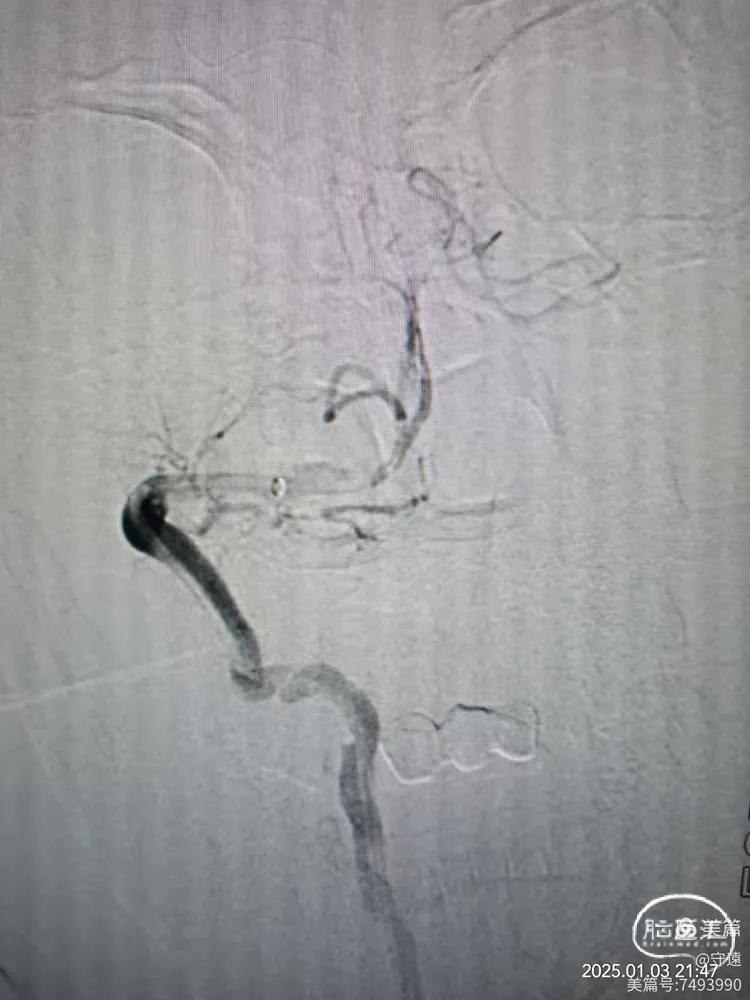

经桡动脉造影:左侧椎动脉起始终部中度狭窄。向颅内供血缓慢,v4段闭塞。

右侧椎动脉为优势椎,血流迟滞,V2以远未显影,考虑V4 闭塞。

右侧椎动脉顺应,更换6F动脉鞘经桡动脉入路行基底动脉开通。

泥鳅导丝导引6FGT68血栓抽吸导管,泥鳅导丝不出头,内芯支持抽吸导管到达V3段。

踹马桶抽吸出小块硬质血栓。

微导管造影显示Ⅴ4狭窄。

微导丝携带2.5*15mm球囊在V4~基底动脉下段扩张。

撤出球囊血管,造影显示再次闭塞,考虑夹层或回弹可能。

球囊穿梭:跟进抽吸导管至狭窄部位,再次输送球囊至狭窄部位。球囊半含状态下再次在7个大气压下扩张。

撤出球囊,踹马桶抽吸出暗红色血栓。

微造影显示:血管再通

回撤导管至V3段造影,狭窄不明显,血流通畅。

回撤至椎动脉起始段造影血流通畅,左侧大脑后似有少量血栓逃逸,推注替罗非班10mL,结束手术。